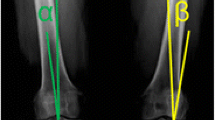

Posterior laxity was evaluated by conventional stress radiographs at 90° of flexion using a stress device (GA II stress device; Telos, Weiterstadt, Germany) with a posteriorly directed force of 150 N at the level of the tibial tuberosity. Perpendicular to the joint line, the midpoints between the most posterior contours of the medial and lateral femoral condyles and tibial plateaus were established [18, 32]. The distance between these two points of the injured side was compared to the distance of the uninjured contralateral knee, henceforth referred to as the posterior tibial translation (PTT).

The TS is defined as the angle between the posterior inclination of the tibial plateau and a line perpendicular to the diaphyseal shaft axis. The diaphyseal shaft axis was determined according to Dejour and Bonnin [7] using two midpoints between the anterior and posterior tibial cortex; one at 5 cm below the tibial tuberosity and the other one 15 cm below the tibial joint line. Although the best available radiographs were chosen, not all included enough tibial shaft to determine the width of the shaft at a distance of 15 cm distal to the joint line. In these instances, the most distal width was measured based on the aforementioned conditions (Fig. 1).

Measurement of the PTT (a). The PTT (asterisk) is defined as the distance between the mean posterior contours of the femoral condyles and the tibial plateau; measurement of the TS (b). The TS (asterisk) is defined as the tangent line to the medial tibial plateau and a line perpendicular to the longitudinal tibial axis